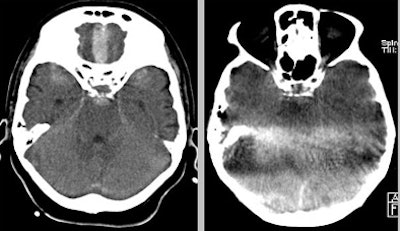

| Infratentorial subarachnoid hemorrhage (SAH) is missed at flat-panel CT. |

For visibility of any SAH in the supratentorial area, flat-panel CT yielded sensitivity of 88% (68%-97% CI Clopper-Pearson) and specificity of 83% (36% to 100% CI Clopper-Pearson), Celedin said. For detecting SAH 5 mm and larger, flat-panel CT yielded one false negative and five false positives, with sensitivity of 93% (68%-100% CI Clopper-Pearson) and specificity of 76% (38% to 88% CI Clopper-Pearson).

For detecting intraventricular blood, there were eight false negatives and three false positives at flat-panel CT, with sensitivity of 58% (33% to 80% CI) and specificity of 73% (39% to 94% CI), Celedin said.

The overall sensitivity of flat-panel CT was better for the supratentorial region compared to the infratentorial region, Celedin said, yet without reaching statistical significance (p = 0.272).